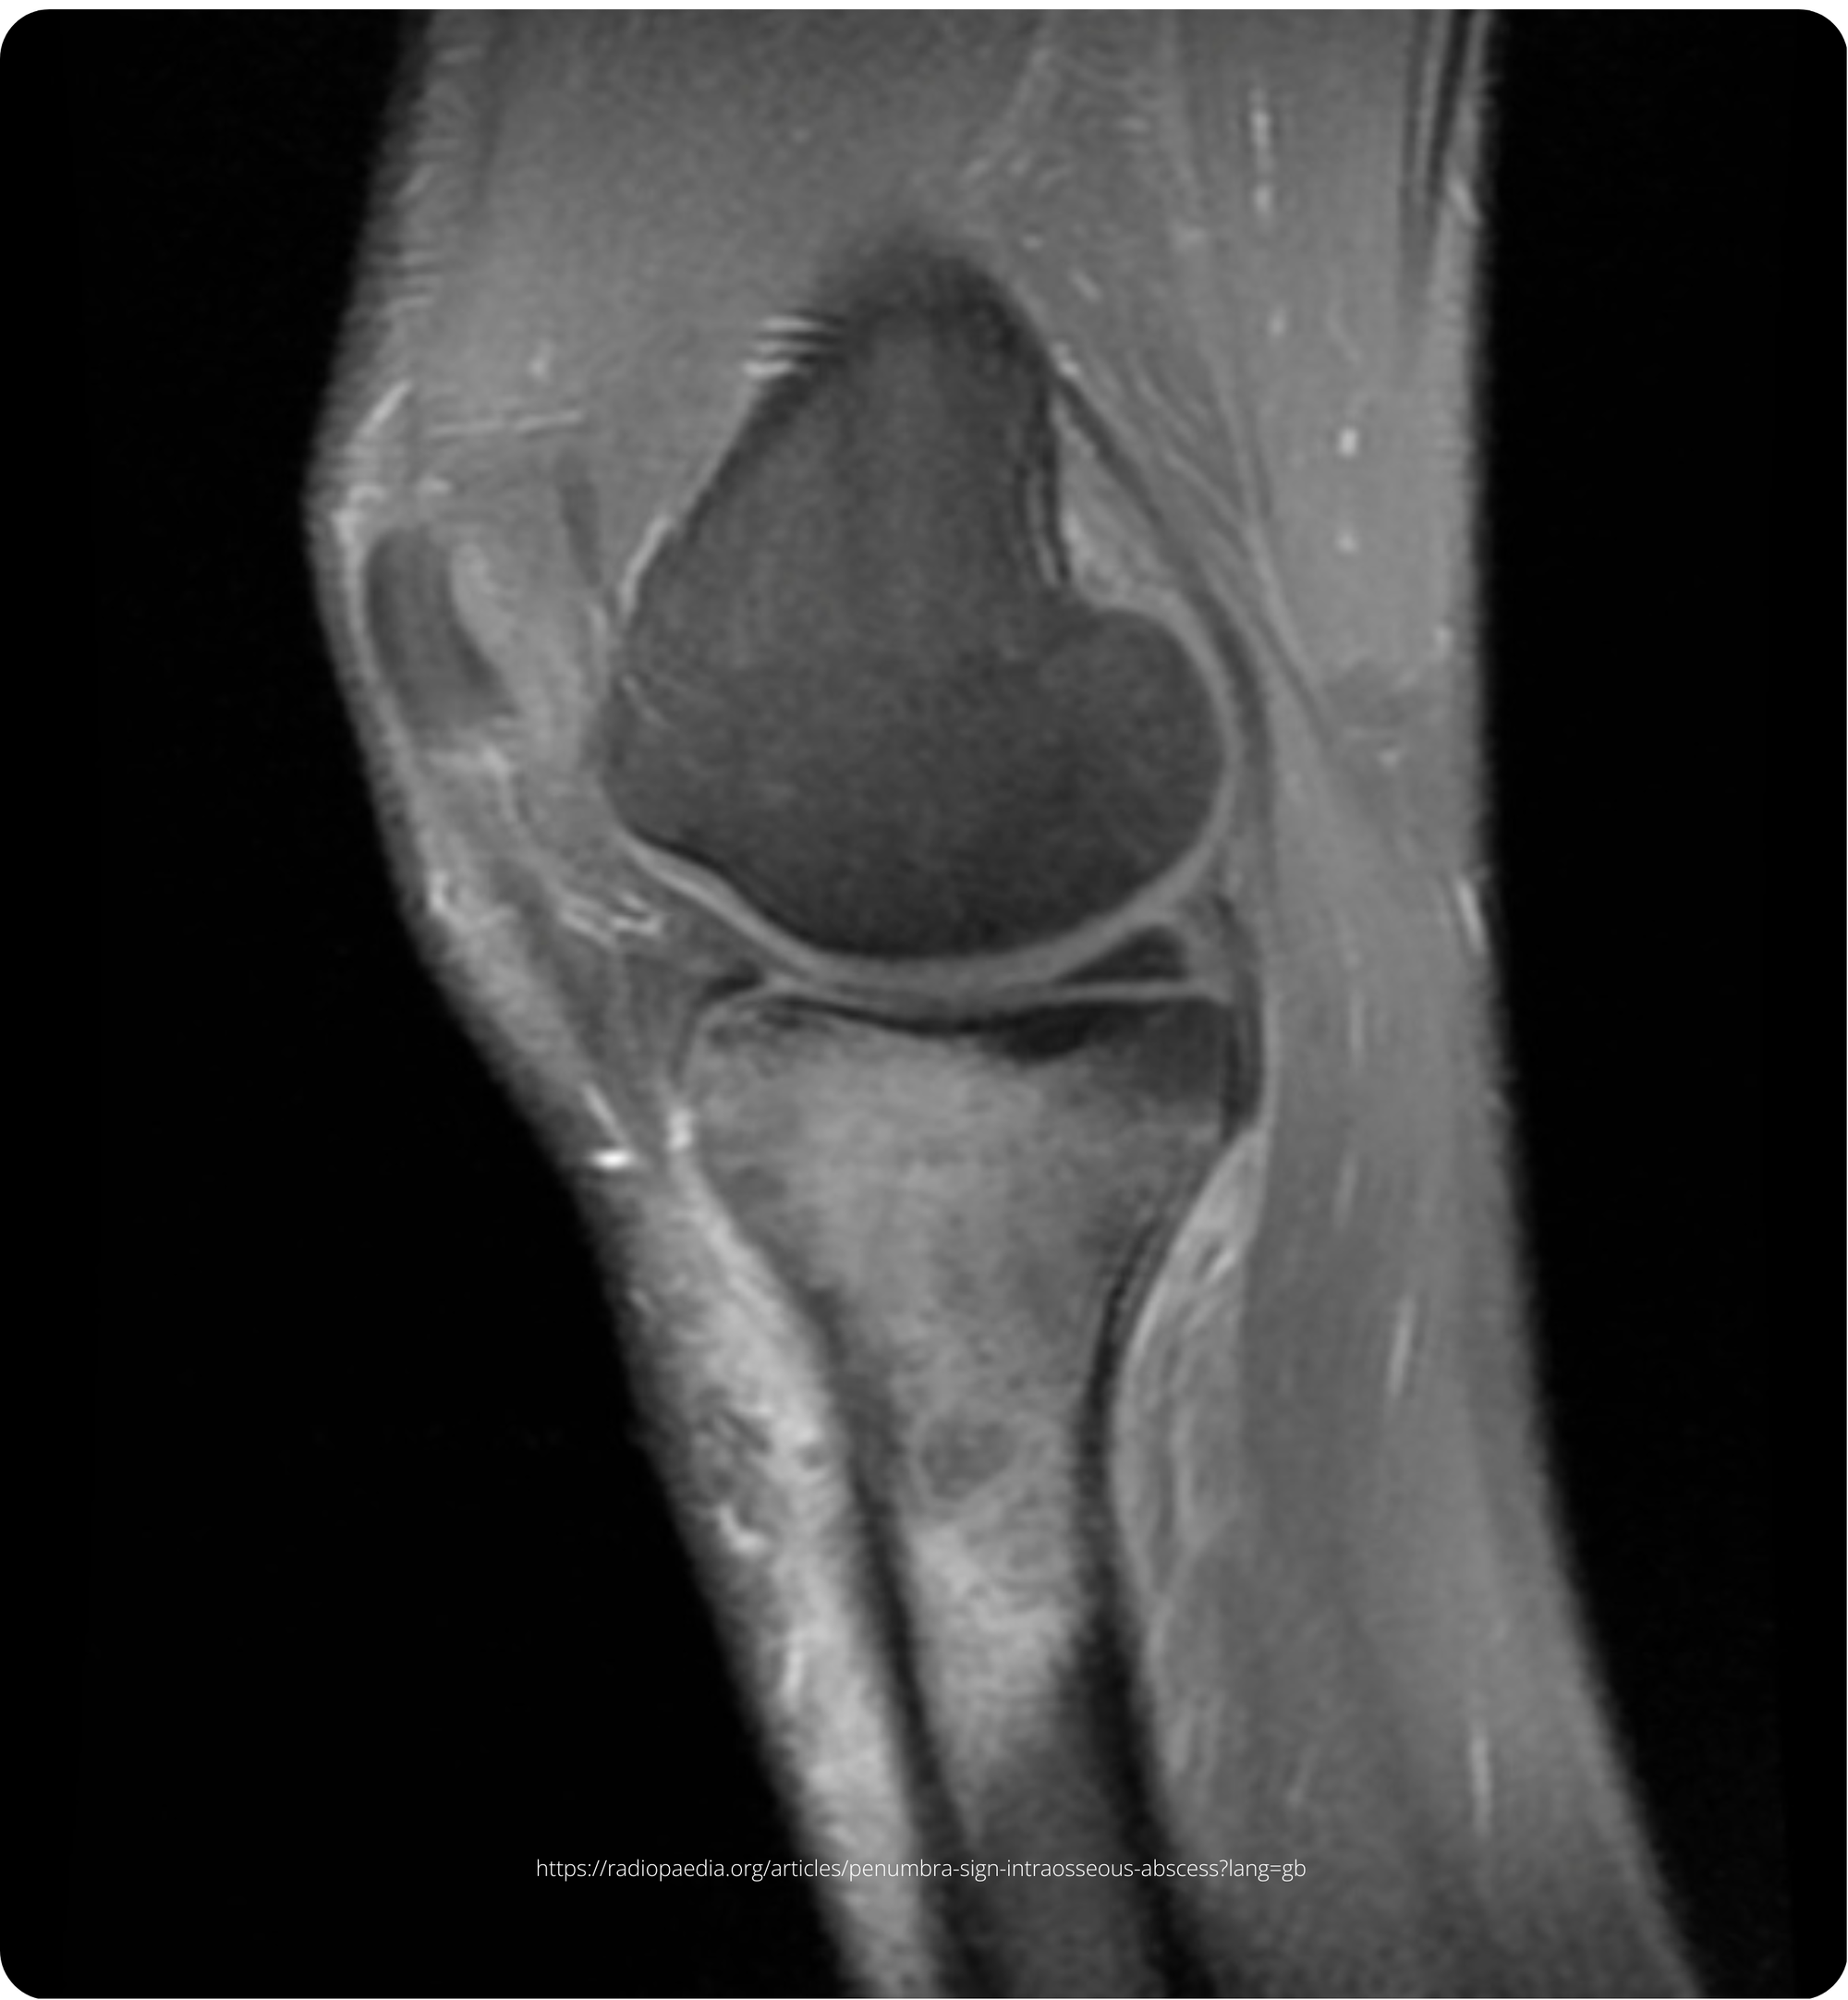

A 70-year-old active runner, previously treated with internal fixation for an open tibial fracture on his right leg three months ago, now presents with progressive pain, swelling, and difficulty in weight-bearing. His initial injury was managed with a tibial plate fixation and direct wound closure. He reported gradual improvement until six weeks ago when he began experiencing increasing pain and weight-bearing difficulties.